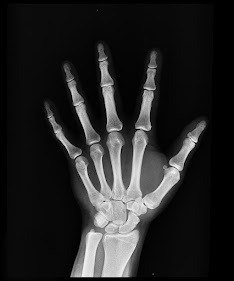

Estas fracturas no suelen implicar traumatismos para la estructura ósea dañada, por lo que a la hora de la recuperación esto les favorece y facilita la rehabilitación. El tiempo de recuperación tras una fractura por estrés oscila entre seis y ocho semanas, en las que tendremos que guardar reposo. Para evitar a la larga estas fracturas, podemos realizar varias cosas para prevenir su patología:

1- Ir al podólogo. Para que nos realice un estudio biomecánico del pie y ver si necesitamos modificar su posición mediante el uso de plantillas para conseguir un apoyo correcto.

2- Vigilar las zapatillas y su desgaste comprobando que tengamos la amortiguación necesaria.

3- Respetar las pautas de descanso que marque nuestro cuerpo y que el entrenamiento no se convierta en una obligación.

4- Fortalecer los músculos en general ya que ellos son los que sostienen a los huesos.

5- También un buen aporte de minerales y nutrientes a través de la alimentación, será clave para mantener la salud de los huesos.